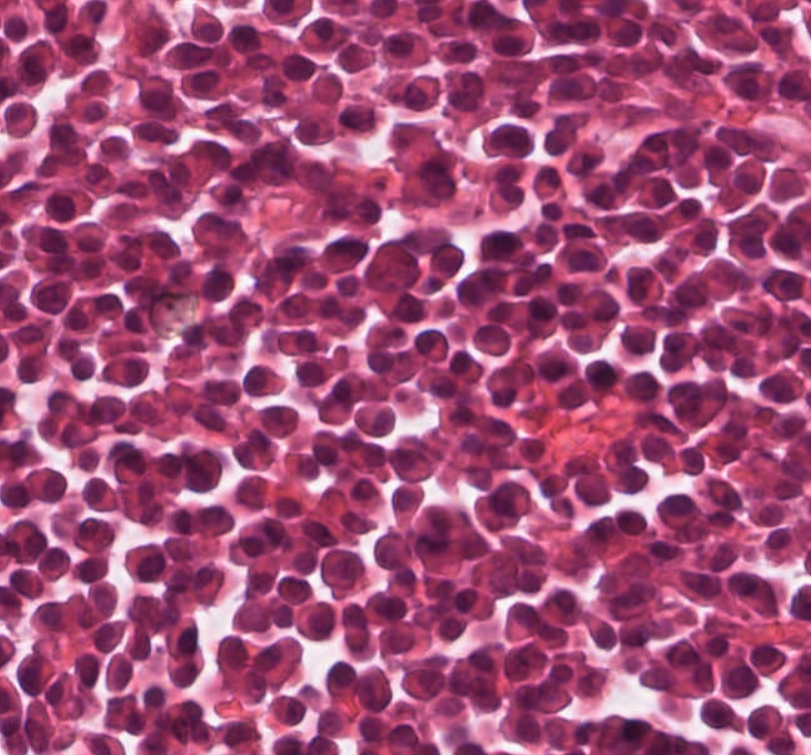

#caseoftheweek 🔬🔬🔬 What is causing a testicular lump in this patient with a raised LDH? View the full slide and thousands of others on the Leeds Virtual pathology website here:virtualpathology.leeds.ac.uk/slides/library… #pathX #PathTwitter #uropath